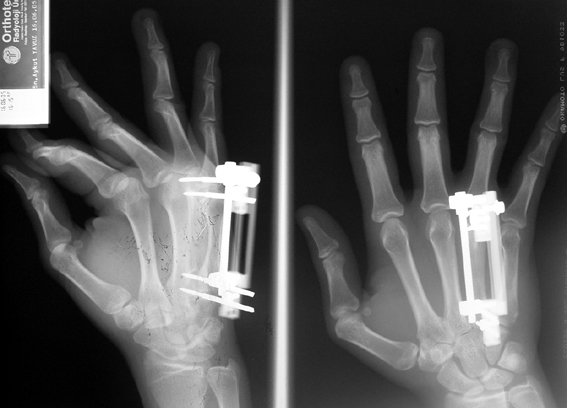

Doğuştan metakarp ve metatars kısalıklarının redavisi için pek çok teknik tanımlanmakla birlikte en çok akut uzatma sonrası kemik uçlarına greft konması ve distraksiyon osteogenezi (kallotasis) kullanılmaktadır. 1 cm.den daha fazla uzatma gereken olgularda kallotasis yöntemi önerilmektedir. Kliniğimizde de metatars ve metakarp uzatma için unilateral eksternal fiksatör ve sirküler eksternal fiksatör yardımıyla distraksiyon osteogenezi yöntemi tercih edilmektedir.